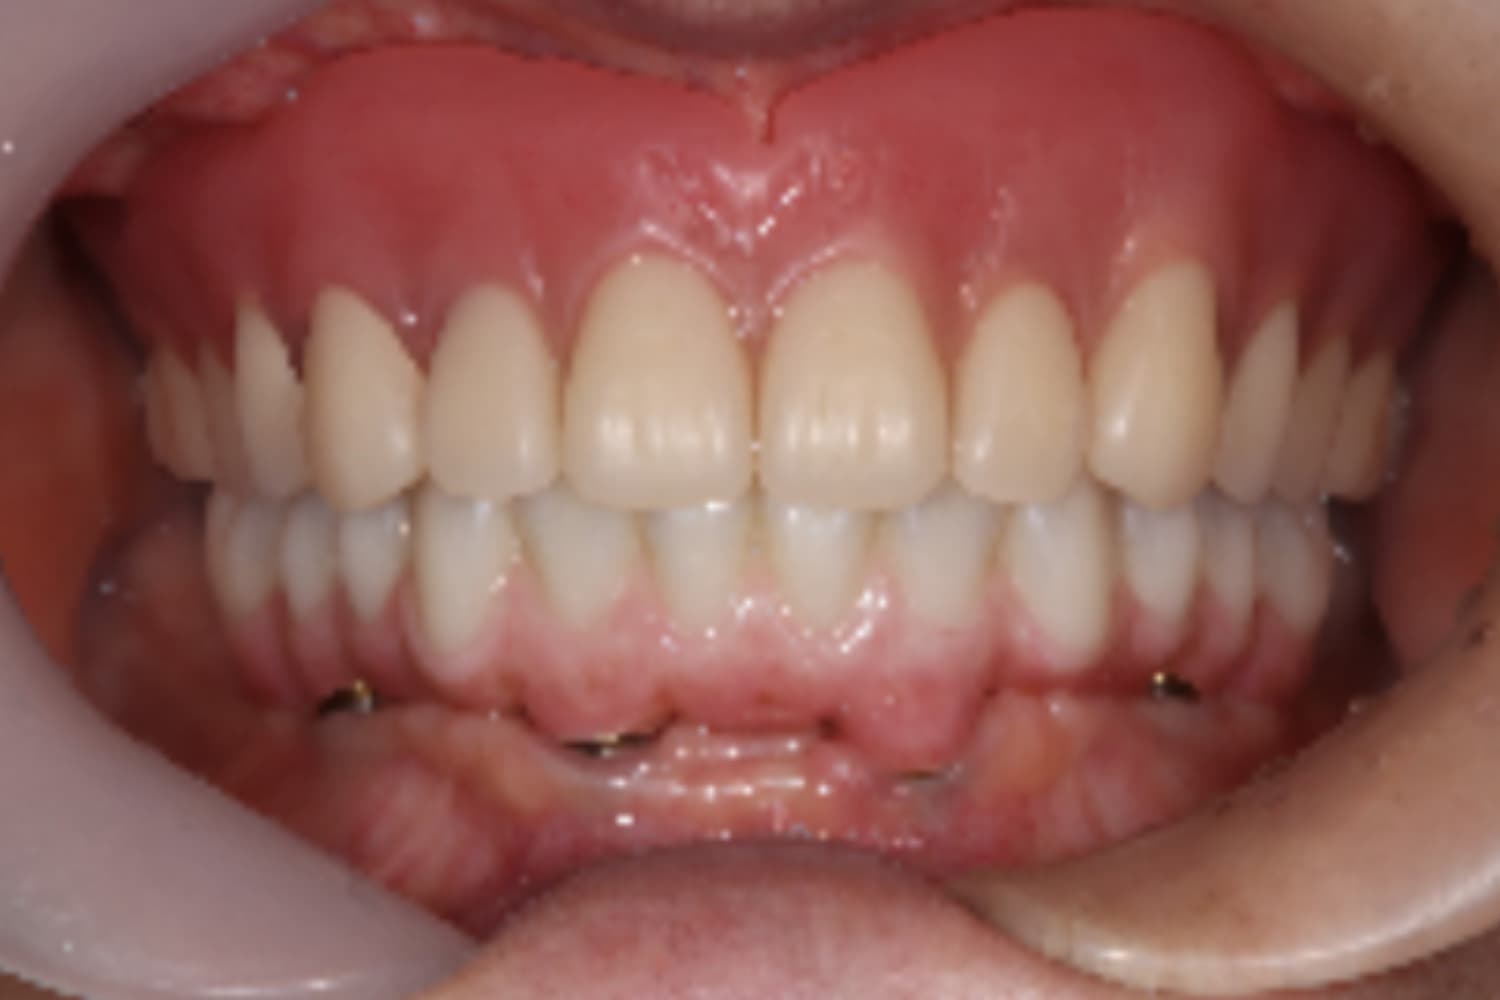

上顎すべてのインプラント治療

Before

After

上顎をインプラント7本で治療

主訴

上顎欠損部にインプラント治療希望

治療期間

18カ月

治療回数

26回

費用

3,450,000円

副作用・リスク

・噛み合わせの崩壊により、治療途中に顎の痛みや顎関節症様の発症リスクがあります。